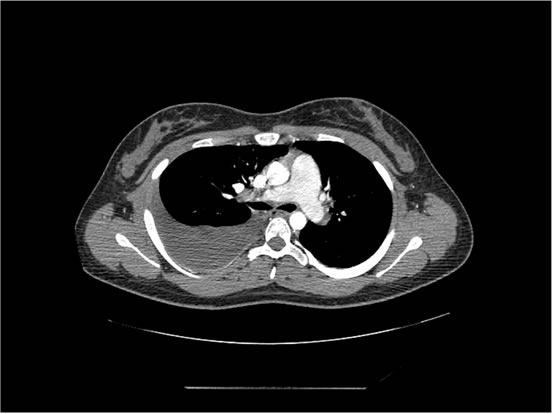

We ordered a CT scan with infusion of the chest

I will show you 12 CT-scan cuts.